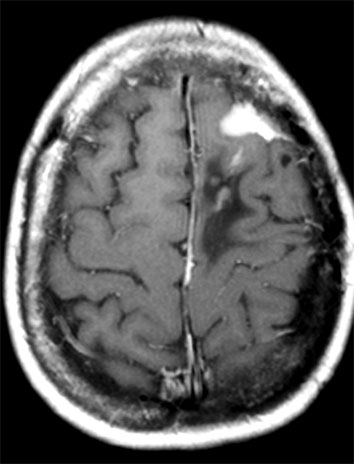

Tratamiento de Meningioma con Radiocirugía Estereotáxica. Paciente había sido operada a craéneo abierto en dos ocasiones, y viene por recurrencia del tumor

Resonancia magnética un año después de la radiocirugía. Note disminución del volumen tumoral